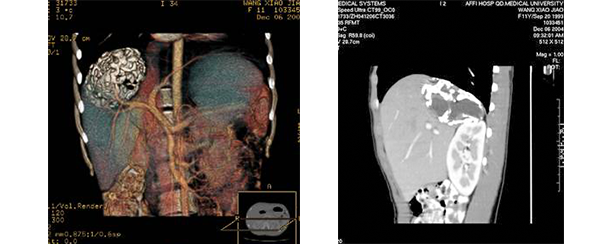

目前常用的检查方法有B超检查、CT、MRI、血管造影等。与其它的腹部肿块的诊断不同,对于小儿肝母细胞瘤血管造影具有重要的意义,可以作为手术前介入治疗的手段,也可为手术提供非常有效的影像学指导,但技术要求高,操作较复杂,且给患儿带来一定的痛苦。近年借助计算机辅助手术系统进行CT原始影像三维重建、手术规划和计算机虚拟手术技术,为精准肝脏手术提供了极为有效的技术支持。

图20:(1)(2) CT增强扫描三维呈像示肝脏畸胎瘤及其其清晰的血供

腹部X线检查,可见肝区的占位病变,肿瘤内如果发现有骨骼、牙齿等影像则能够明确诊断。B超、CT及MRI等可以更清楚地了解病变的范围和性质。见图20,图21。